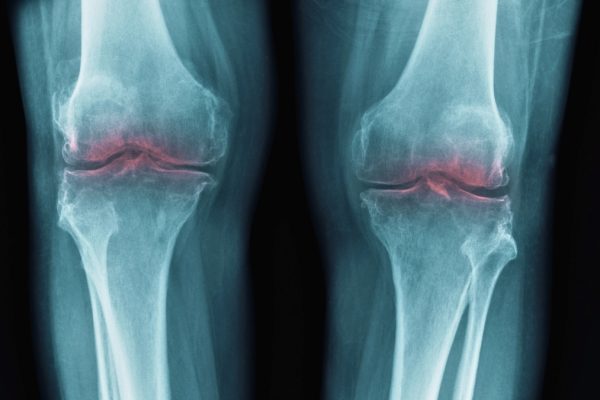

Creșterea Apariției Artrozei la Adulții Tineri, Declanșând Decenii de Disconfort

Una dintre ele, o pasionată alergătoare de maratoane, a dezvoltat artroză de gradul 2 în jurul vârstei de 30 de ani. Mai mulți oameni publici cunoscuți, precum Robbie Williams, Tiger Woods și Andy Murray, au vorbit deschis despre experiența lor cu această condiție la vârste relativ tinere. Artroza este adesea trecută cu vederea ca o…